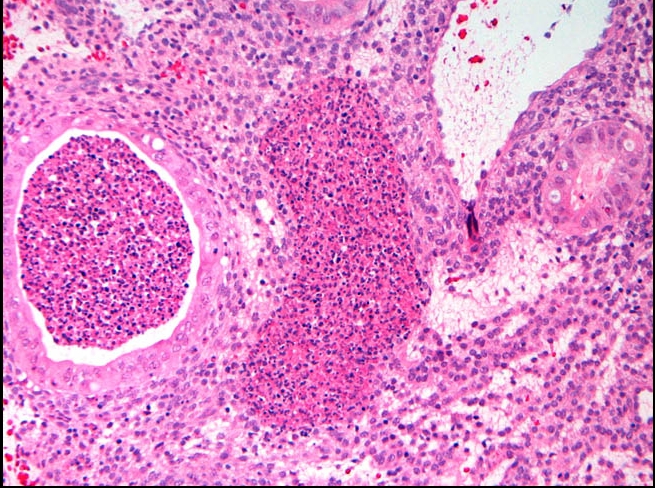

High grade dysplasia (carcinoma in situ) in the uterine cervix. The abnormal epithelium is extending into a mucus gland to the left of centre. This disease can progress to invasive cancer (squamous cell carcinoma) of the cervix:

CIN III

_Carcinoma in situ is characterized by atypical changes extending through the entire thickness of the epithelium.

As it has not yet invaded the basement membrane, it is considered a precancerous lesion.